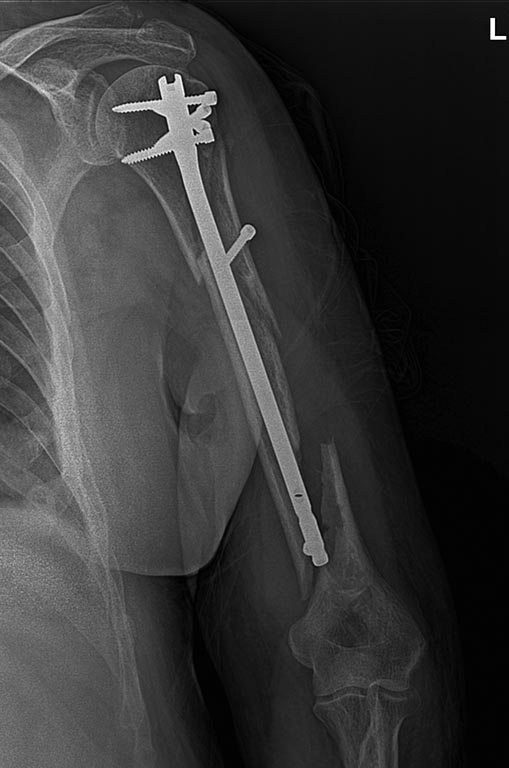

[Ortho] перелом плеча на гвозде

Уважаемые коллеги поступил пациент 2 мес назад у нас биос плеча.упал с

перрона.какие мнения?